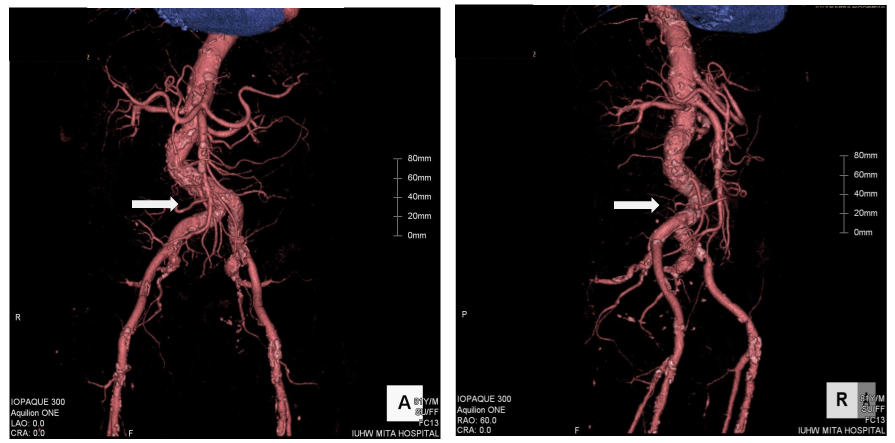

An 81-year old man had been attending a physician at our hospital for several years, because of type II diabetes mellitus, hypertension, and chronic kidney disease. On one regular visit to the doctor, sudden syncope and collapse within the hospital required him to be admitted to the department of internal medicine. The patient recovered consciousness several minutes later and no apparent neurological abnormality could be detected. Cardiovascular examination identified no significant heart murmur. Blood tests showed no evidence of myocardial enzyme leakage, electrolyte disturbance, inflammation, or significant anemia that might be associated with syncope, except for the fact that the troponin I level was just above the upper normal limit (0.11ng/mL). The electrocardiogram also showed no specific changes suggestive of an acute coronary syndrome (ACS). The chest X-ray depicted a status of mild congestion, and echocardiography showed signs of mild hypokinesis of the posterior wall. Brain computed tomography (CT) showed no evidence of fresh infarction or hemorrhage at this point. Enhanced CT from chest to pelvis did not indicate any evidence of aortic dissection or aneurysmal rupture, but there was significant tortuosity of the right common iliac artery and the abdominal aorta below the renal arteries, with severe calcification (Figure 1). The next day’s blood test, however, showed significant increases in the levels of CK (2823IU/L), AST (433IU/L), LDH (1231IU/L), and WBC (132.1×100/µL), signifying the development of acute myocardial infarction. The coronary angiography (CAG) was performed via the right femoral artery, using 5F diagnostic catheters, JL5.0 and JR4, and showed a 90% stenosis in the left anterior descending artery (LAD)#6-7, with TIMI grade III flow, and a total occlusion in the right coronary artery (RCA)#2, with a relatively steep angulations (Figure 2). Accordingly, PCI was performed, treating the RCA occlusion as a culprit on the same day. Since the patient suffered from chronic kidney disease, as indicated by the high creatinine value (1.85mg/dL) and low estimated glomerular filtration rate (21.5mL/min/1.73m2), we selected the right femoral artery for access, in order to preserve the radial arteries for shunts in the case of hemodialysis. Although the left femoral artery was also considered as a candidate for access, the weak pulsation of both left popliteal and dorsal arteries kept us from choosing it. Even though the enhanced CT indicated this case as a high complicated case about its vessel tortuosity, we continued the procedure with disregard for this information at this point. A 7F super-long sheath was inserted in order to elongate the tortuosity of the common iliac artery, but the sheath became kinked at the tortuous point. Consequently, the guiding catheters could not be manipulated effectively, because of the tight constriction of each catheter by the sheath. We sized down the catheter from 7 F to 5F (7F JR4.0, SAL0.75, and AL1.0, 6F AL1.0, and 5F JR4.0) so as to allow more space, but this was unsuccessful. Finally, we decided to change the access site to the right brachial artery with a 6F sheath, and we selected a 6F EBU3.5 as a guiding catheter. As we carefully manipulated the catheter, in which the Radiocast® Guide wire (TERUMO, Tokyo, Japan) was still inserted, the tip of the catheter passed into the RCA, though not very deeply. The ULTIMATEbros3® guidewire (ASAHI INTECC, Aichi, Japan) was successfully advanced to #4AV with support from a microcatheter, (Finecross® MG, TERUMO, Tokyo, Japan), after an attempt to cross the lesion witha floppy guidewire had failed (Joker®, Japan Lifeline, Tokyo, Japan) (Figure 3). The lesion was then dilated using a 1.2mm semi-compliant balloon (TENKU®, ST. JUDE MEDICAL, St Paul, MN, USA) followed by a 2.5mm balloon (Lacrosse LAXA®, GOODMAN, Aichi, Japan). At this point, we established that there was recovery flow of TIMI II, with huge amounts of floating thrombus. Unfortunately, the aspiration was completely unsuccessful, so we decided to compress the thrombus as far as possible using a large-sized balloon. From the occlusion site to distal portion#3, the vessel was entirely dilated by a 3.5mm semi-compliant balloon (Sprinter® legend RX, Medtronic, Minneapolis, MN, USA), followed by a 5.0mm non-compliant balloon (NC Quantum Apex®, Boston Scientific, Natick, MA, USA). Finally, we determined that it would be better to terminate the procedure at this point without any stent deployment, because of the abundance of fresh thrombus throughout the RCA (Figure 4).

Figure 1 Three-dimensional image from enhanced computed tomography. The white arrows indicate significant tortuosity of the right common iliac artery. Left: antero-posterior projection. Right: right anterior-oblique projection.